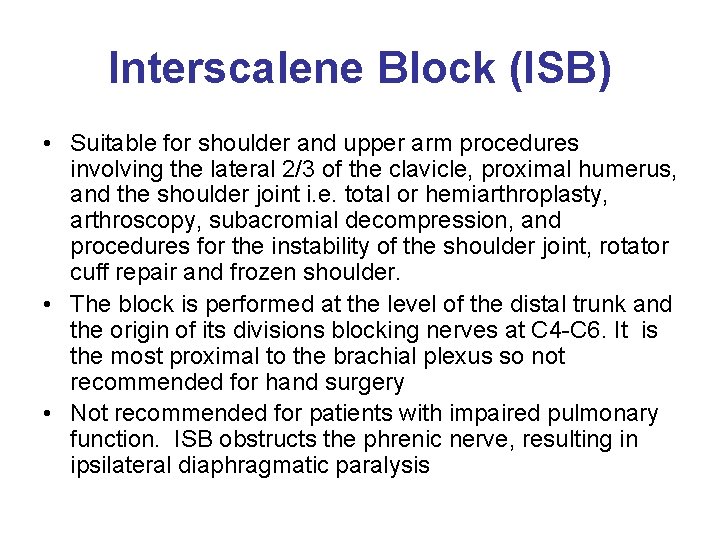

Interscalene Block (ISB) • Suitable for shoulder and upper arm procedures involving the lateral 2/3 of the clavicle, proximal humerus, and the shoulder joint i. e. total or hemiarthroplasty, arthroscopy, subacromial decompression, and procedures for the instability of the shoulder joint, rotator cuff repair and frozen shoulder. • The block is performed at the level of the distal trunk and the origin of its divisions blocking nerves at C 4 -C 6. It is the most proximal to the brachial plexus so not recommended for hand surgery • Not recommended for patients with impaired pulmonary function. ISB obstructs the phrenic nerve, resulting in ipsilateral diaphragmatic paralysis

Interscalene Block • The approach to the brachial plexus lies in the neck between the interscalene muscle and the clavicle. • The patient lies supine with the head facing away from the side to be blocked. • Landmarks include the sternocleidomastoid muscle, external jugular vein, and the cricoid cartilage. The level of the cricoid cartilage corresponds to the C 6 vertebral body where the interscalene block is administered. • The needle is inserted into the interscalene groove in a slightly medial, caudal, and posterior direction to avoid the vertebral column and vascular structures. • Provides spread to the nonbrachial plexus Supraclavicular nerve which supplies sensory innervation to the cape of the shoulder. May not anesthetize the entire posterior aspect of the shoulder.